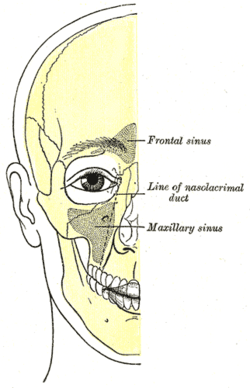

Sagittal section of nose mouth, pharynx, and larynx. Outline of bones of face, showing position of air sinuses.

Outline of bones of face, showing position of air sinuses. Paranasal sinuses